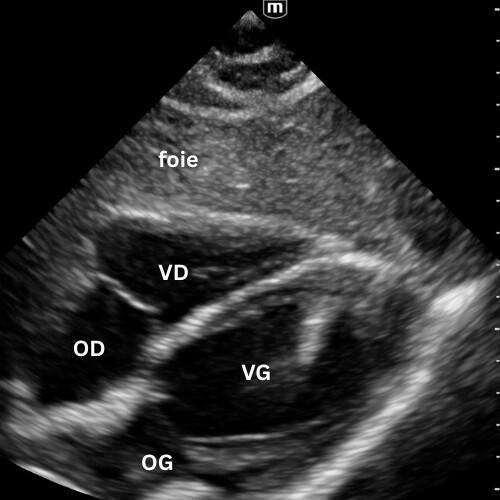

🔹 Vue Parasternale Petit Axe

→ La contraction est-elle harmonieuse ?

Même point d’appui que pour le parasternal grand axe, rotation à 90°, marqueur vers l’épaule gauche.

On observe la coupe circulaire du VG et du VD.

Un VG rond, contractile et homogène = fonction normale.

Un VG aplati ou en “D” = surcharge droite (embolie pulmonaire, HTP, tamponnade).

Une zone hypokinetique/akinetique = ischémie segmentaire.

Vue reine pour la fonction systolique et le septum interventriculaire.

Un léger mouvement de bascule permet d’explorer trois niveaux distincts :

- le plan de la valve mitrale

- le plan des muscles papillaires

- le plan de la valve aortique avec son aspect caractéristique en « signe Mercedes ».